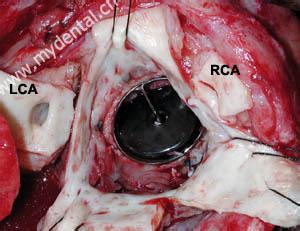

感染性心内膜炎有一定的好发部位,多发生于血流冲击或局部产生涡流的部位,如二尖瓣关闭不全的心房面,主动脉瓣关闭不全的心室面,室间隔缺损的右心室面动脉导管未闭的肺动脉内膜面等。

亚急性感染性心内膜炎基本病理变化有病损的心瓣膜或心内膜上有赘生物形成,赘生物由纤维蛋白,血小板及白细胞聚集而成,细菌隐藏于其中,该处缺乏毛细血管,较少吞噬细胞浸润,因而药物难以达到深部,且细菌难以被吞噬,此为细菌得以长期存在的原因。

赘生物所附着的瓣膜有炎性反应及灶性坏死,其周边有淋巴细胞,纤维细胞及巨细胞浸润。坏死细胞周围有新生毛细血管,结缔组织及肉芽组织,当炎症消退,赘生物纤维化,表面为内皮细胞所覆盖,经治疗痊愈的病例,三个月才能完全愈合,未治愈的病例,愈合与炎症反应交叉存在。赘生物大而易碎,脱落可致脏器及周围动脉栓塞,如肾、脑、脾、肠系膜及四肢等,先心病并感染性心内膜炎病例,多并发肺栓塞,局部细菌滋长可使瓣叶产生溃疡或穿孔,腱索及乳头肌断裂及细菌性动脉瘤。抗原-抗体复合物在肾血管球沉积,可发生肾血管球性肾炎,由于免疫反应引起小动脉内膜增生,阻塞及小血管周围炎,表现为皮肤及粘膜的淤点,发生于手指、足趾末端的掌面,稍高于皮面,有压痛,5-15mm大小,称奥氏(Osler)结节,后掌及足趾有数毫米大小的紫红色斑点,称为Janeway氏结节。